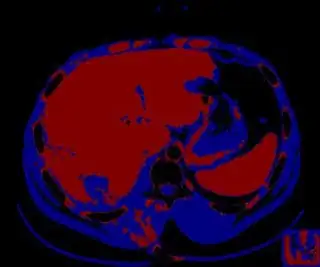

I extracted liver for this sample image and the output is like this Output image for sample image. My implementation code is

Without using fixed thresholds, you can try to cluster the image by gray levels. As a preprocessing step, I would suggest using morphological opening to make the difference of gray levels of the neighboring pixels small, so you have less noise in the clustered image.

Below I apply two successive morphological openings to the image using a 3x3 circular kernel, and then apply k-means clustering to the gray levels. From your sample images and some I found on the internet, I decided to set k = 4. If you are using high-resolution images, first downsample them to dimensions ~400-600. Otherwise the morphological operation may not have a significant effect, and the k-means will be slow.

Below are some of the opened and segmented images. Of course there's more to be done in terms of

• separating out the liver region

• generalizing this to a large dataset

but hope this is at least a starting point.

Update You might be able to narrow down the region or interest by filtering out the darkest and the lightest regions from the segmented image. For this, use the k-means cluster centers, check for the extreme values (max and min) and remove the corresponding k values from the labeled image. Then you can look for large structures to the left of the result image. Worst case, you might get a hole on the left side when the extreme region filtering goes wrong. I've updated the code and results.